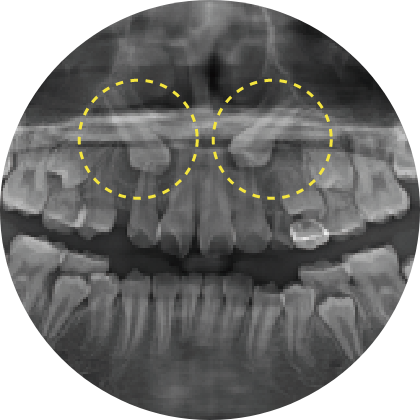

예방교정

적절한 시기의 교정으로 아이의 치아를 건강하게!

이 시기에 교정 검진을 받으면, 성장과 발달을 고려한 적절한 치료 계획을 세울 수 있습니다. 적절한 시기에 치료하지 않으면 나중에 교정의 난이도가 높아질 수 있어, 빠른 시일 내에 교정 검진을 받는 것이 중요합니다.